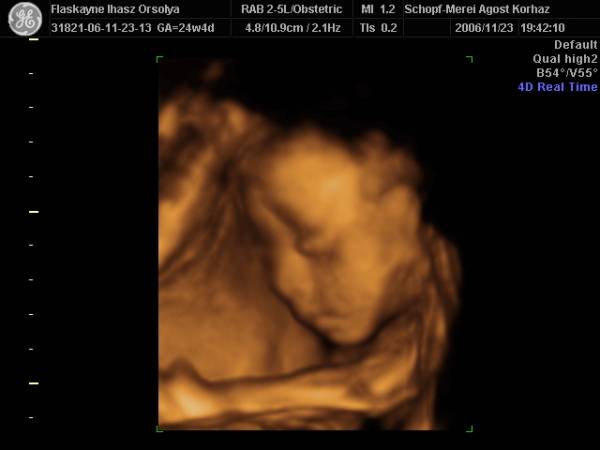

És aznap délután 4D!!!